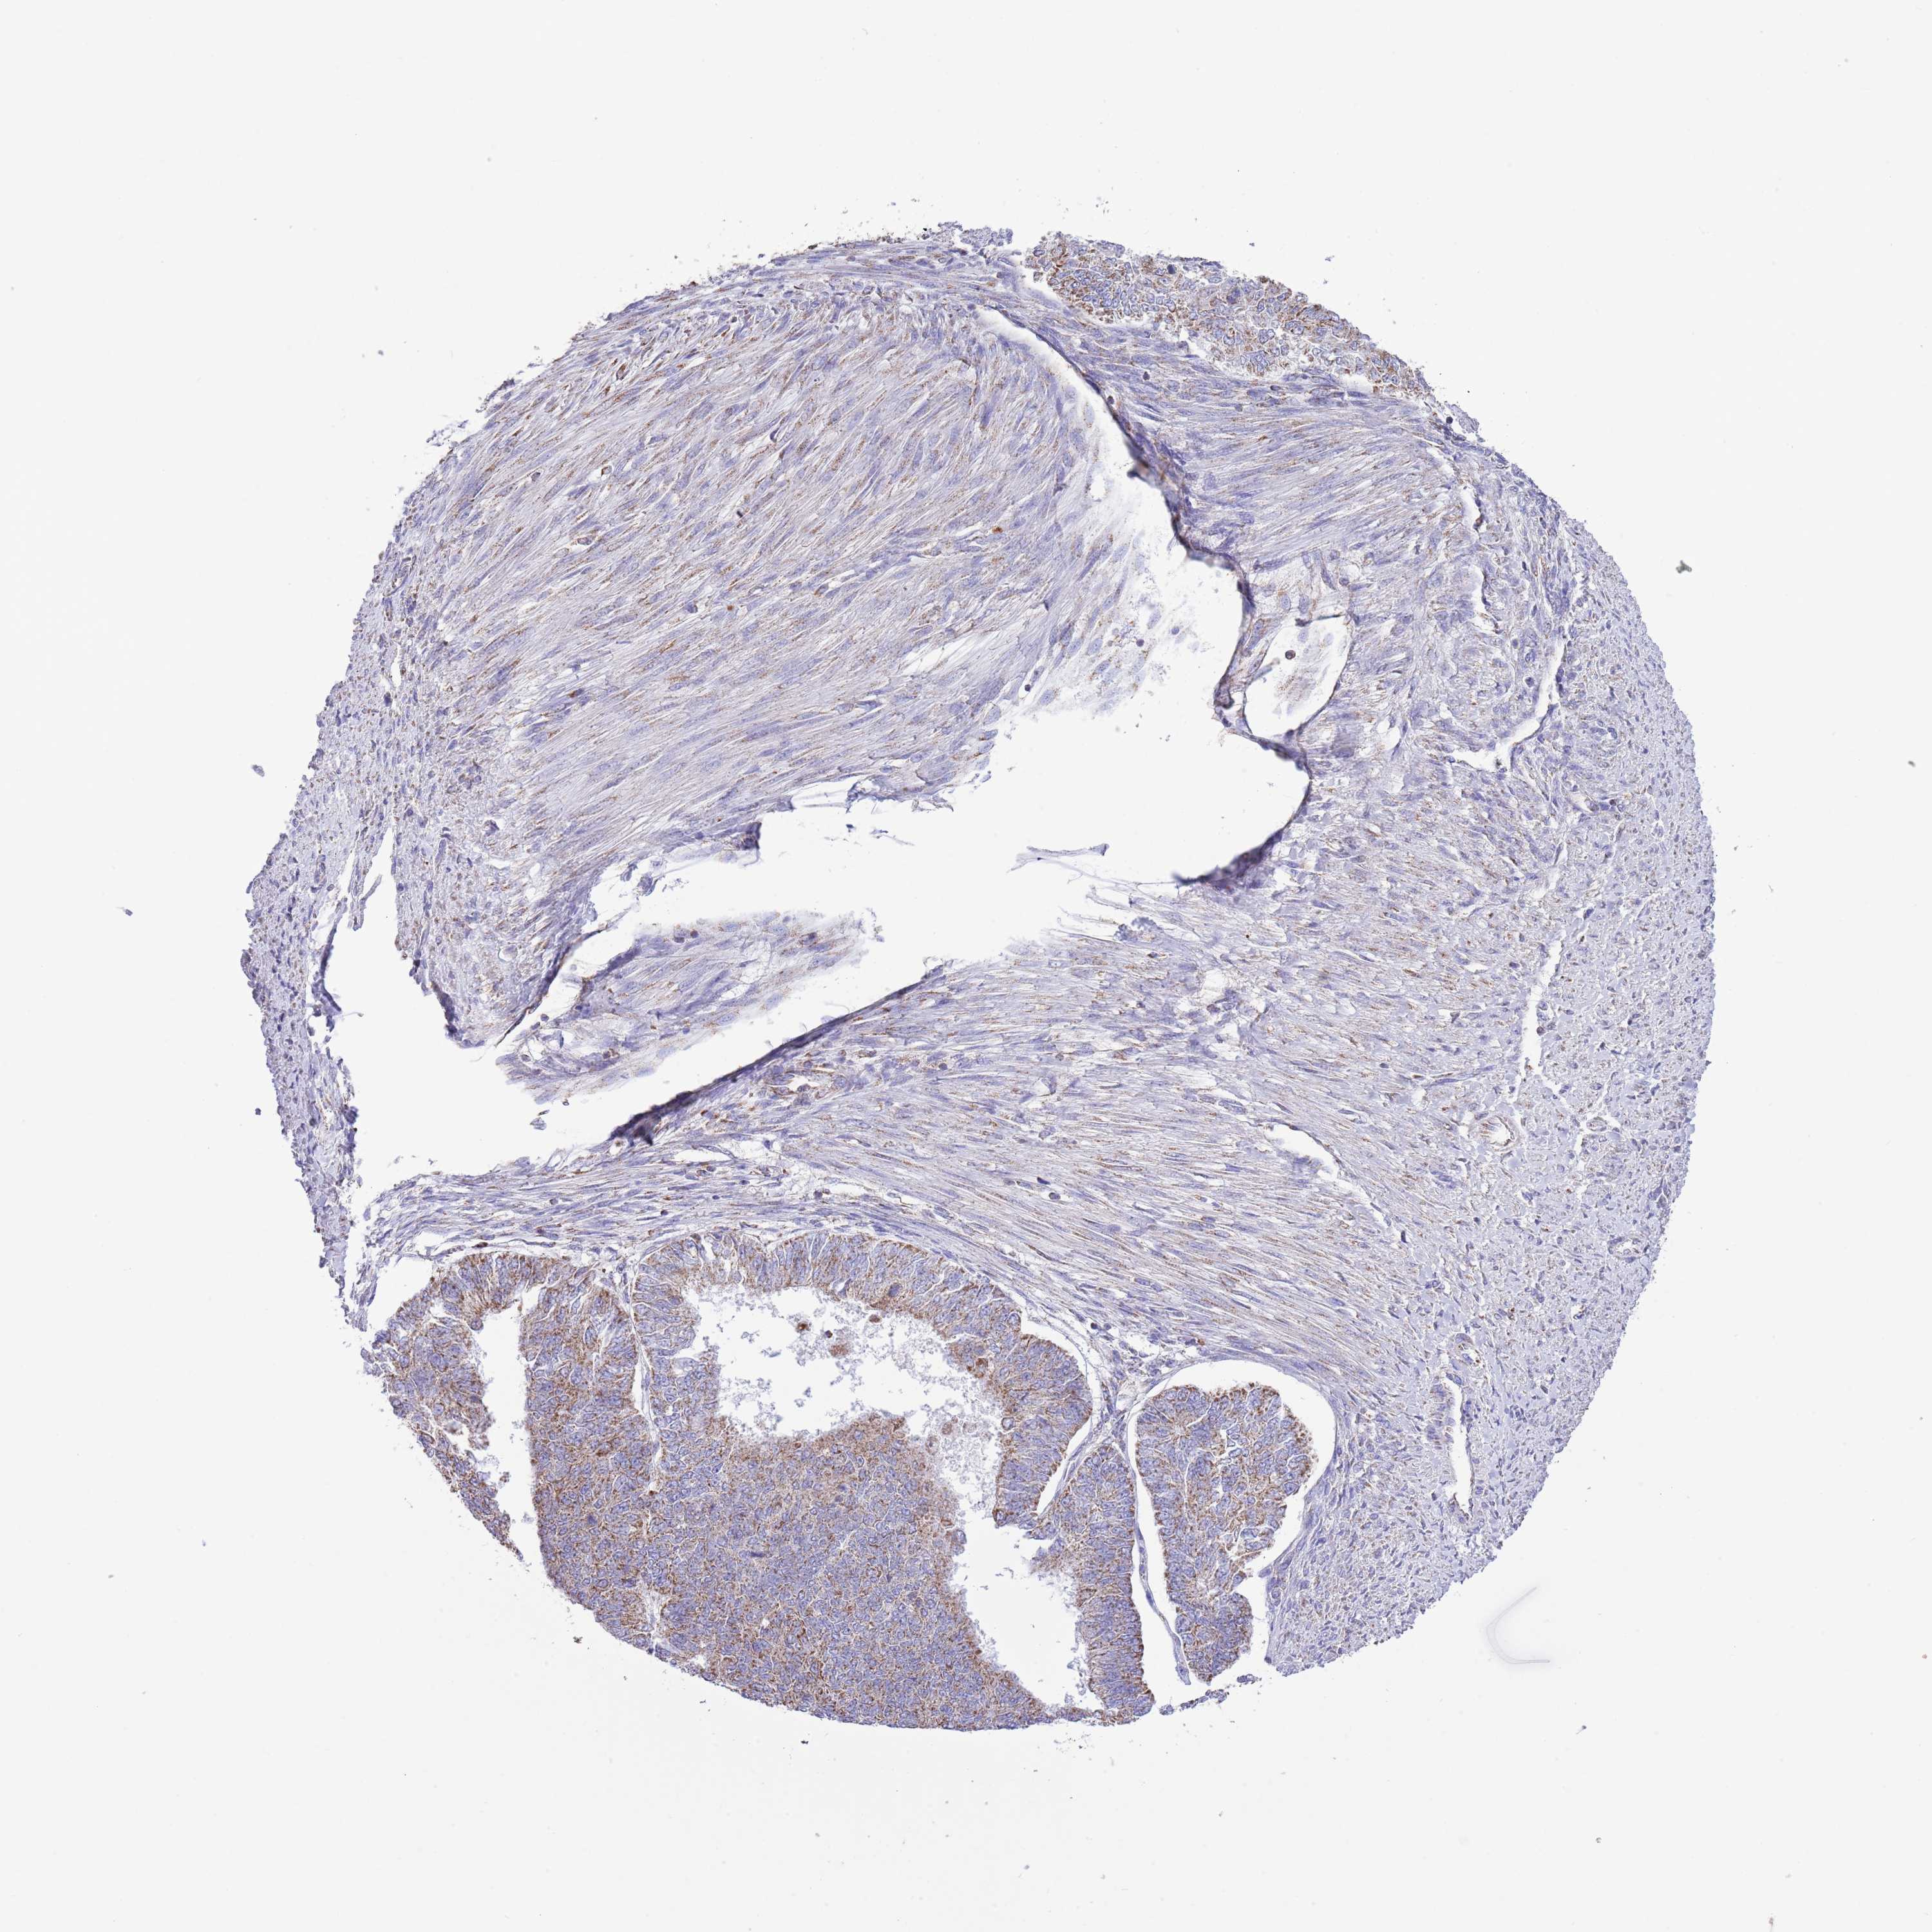

ENDOMETRIAL CANCER - Protein expressioni

A mouse-over function shows sample information and annotation data. Click on an image to view it in a full screen mode. Samples can be filtered based on level of antibody staining by selecting one or several of the following categories: high, medium, low and not detected. The assay and annotation is described here.

Note that samples used for immunohistochemistry by the Human Protein Atlas do not correspond to samples in the TCGA dataset.

Antibody stainingi

Antibody staining in the annotated cell types in the current human tissue is reported as not detected, low, medium, or high, based on conventional immunohistochemistry profiling in selected tissues. This score is based on the combination of the staining intensity and fraction of stained cells.

Each image is clickable and will lead to virtual microscopy that enables deeper exploration of all samples and also displays staining intensity scores, fraction scores and subcellular localization as well as patient and tissue information for each sample.

Antibody HPA048654

Staining

High

Medium

Low

Not detected

Intensity

Strong

Moderate

Weak

Negative

Quantity

>75%

75%-25%

<25%

None

Location

Nuclear

Cytoplasmic/membranous

Cytoplasmic/membranous,nuclear

Adenocarcinoma, NOS